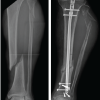

At the Tertiary Care Hospital in Bandra, Mumbai, 52 tibial shaft fractures were treated with tibial IMN between July 2019 and December 2020. The vast majority of tibial fractures were treated with a semi-extended technique, with the exception of grade IV arthrosis in the immovable PF joint (PFJ). Surgeons working alone performed all of the SP tibial IMN procedures. In this nonrandomized retrospective analysis, 52 patients (44 men and 8 women; mean age 47.2 years; range, 18–75 years) getting semi-extended care through the SP route were included in the study. For every patient, information on gender, age, limb side, and fracture classification was noted. The AO system was utilized for the classification of fractures. Written informed consent was given by each patient. Within 48 h of arriving at the emergency hospital, all fractures were treated by SP route tibial IMN. Initially, the patients received spinal anesthesia. Before the procedure, a pneumatic tourniquet was inflated. Next, the leg was prepared in a semi-extended posture with 15° of flexion. An SP midline incision was made 3 cm from the superior to proximal pole of the patella. The quadriceps tendon was incised along the midline to reach the SP pouch (Fig. 1). To preserve the PFJ, a trocar was implanted through the SP portal into the tibia’s anterosuperior border (Fig. 2). By passing a K-wire through the trocar under fluoroscopic guidance, the starting position of the nail was ascertained. In line with the McConnell et al. approach [10], the starting points were determined to be immediately anterior to the ventral edge of the joint surface on the sagittal plane (Fig. 3) and medial to lateral intercondylar tubercle in the coronal plane. A biplanar fluoroscopy system was used to verify the K-wire’s location. During the procedure, the tibial fracture was kept to a minimum and reduction maintenance was accomplished in the semi-extended position. The intramedullary canal was prepped for nail insertion by inserting the guide wire into it following proximal reaming. Next, the intramedullary canal was used to insert the nail (Fig. 4).

Distal locking and proximal locking screws were done under fluoroscopic guidance with jig (Fig. 5). Final position of implant was examined by fluoroscopic images (Fig. 6). Following surgery, patients were encouraged to gradually bear more weight. Range of motion in the knees and ankles was supported. Furthermore, physical therapy helped to progressively strengthen the quadriceps. Angulation, PF arthritis, fracture healing, and accuracy of fracture reduction were measured on X-rays. Lower extremity functional scale was used to measure functional outcome. Patients provided those measurements during the most recent follow-up check-up. Non-union, comorbidities, and fracture healing times were observed.